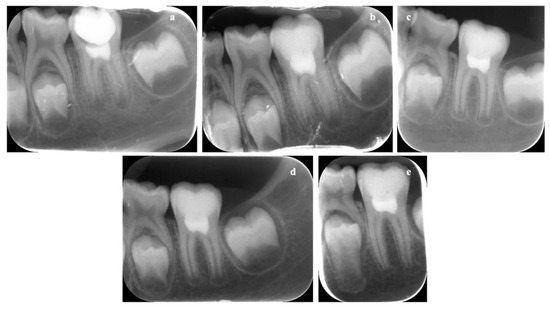

3.8. In Vivo Results